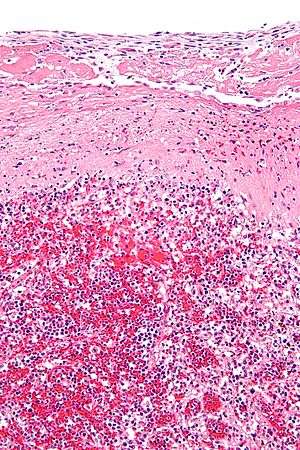

In histopathological medical usage, a hyaline substance appears glassy and pink after being stained with haematoxylin and eosin — usually it is an acellular, proteinaceous material. An example is hyaline cartilage, a transparent, glossy articular joint cartilage.

Arterial hyaline is seen in aging, high blood pressure, diabetes mellitus and in association with some drugs (e.g. calcineurin inhibitors). It is bright pink with PAS staining.